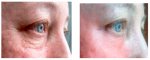

1 пик 2 года назад, второй соответственно сейчас

Более четкий второй пик*